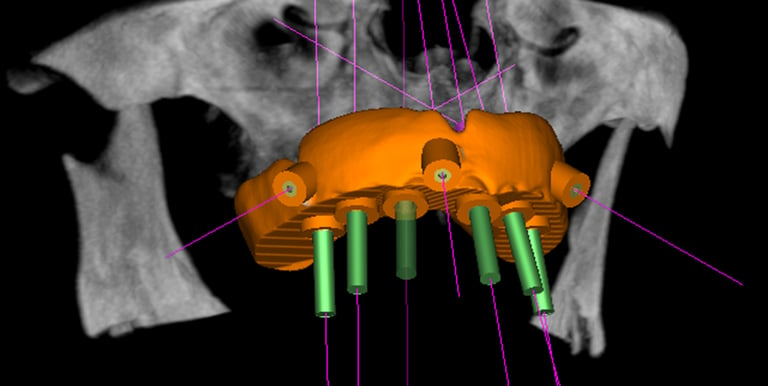

Implante sem corte ou bisturi já é uma realidade

É possível planejar e fazer implantes dentários sem a necessidade de cortes ou bisturis. Utilizando a tecnologia digital, o procedimento se torna mais preciso e menos invasivo.

O planejamento é feito em um computador com base em tomografias e escaneamentos da boca do paciente. Com esses dados, um guia cirúrgico é impresso em 3D. Esse guia se encaixa na boca do paciente e mostra o local e o ângulo exatos para a inserção do implante, evitando a necessidade de abrir a gengiva com bisturi.

A cirurgia é mais rápida, tem um pós-operatório mais tranquilo e com menos inchaço e dor. A recuperação também costuma ser mais rápida, e o resultado final é mais estético.

Planejamento digital do implante

O planejamento digital permite fazer a cirurgia sem bisturi e em poucos minutos.

Planejamento virtual feito sobre um modelo escaneado da boca do paciente. Fazendo os procedimentos serem de maior precisão.